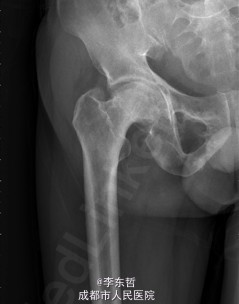

患者男,62岁,因“双髋疼痛4年,加重伴活动受限1年”入院。病员诉入院前4年无明显诱因出现双侧髋部疼痛,行走后疼痛加重,疼痛能忍受,双侧髋部无红肿,皮温不高,无畏寒、发热,休息后疼痛能自行缓解,无夜间疼痛,在当地医院行止痛药内服、理疗治疗,疼痛稍缓解。逐渐加重,1年前双侧髋部疼痛、跛行明显加重,左髋活动受限,行走困难,给予对症治疗症状无明显改善,遂到我科门诊就诊,X线片提示:双侧股骨头坏死,建议手术治疗,故于今日以“双侧侧股骨头坏死”收入我科进一步治疗。

查体:生命体征平稳,心肺腹未见异常;跛行,双左下肢较右下肢短缩1cm,左、右腹股沟中点深压痛,左、右髋叩击痛,左髋屈20°,伸0°,外展10°,内收10°,右髋屈60°,伸0°,外展20°,内收20°。双髋内、外旋活动受限,诱发疼痛,左侧重。 辅助检查:x线片示双侧股骨头坏死、塌陷变形,左侧明显,左髋半脱位。

初步诊断:1、左侧股骨头坏死伴内收肌挛缩(Ficat IV期);2、右侧股骨头坏死(Ficat IV期);3、右膝骨关节炎伴外翻畸形;入院后积极完善术前检查及准备,择期行手术治疗。